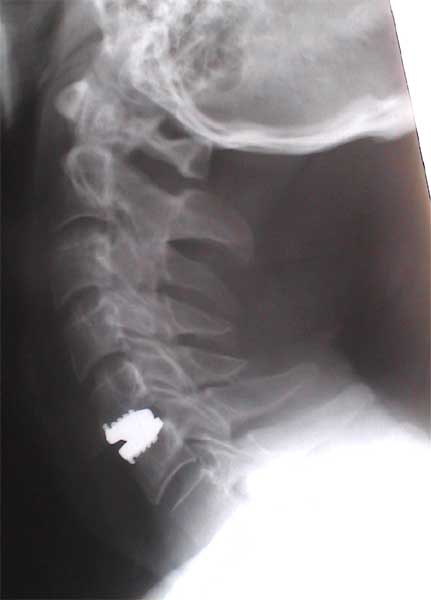

Bild 1 - 4 von links nach rechts

Bild mit Prestige-Prothese

monosegmentale Versorgung

bisegmentaler Versorgung - Retroflexion